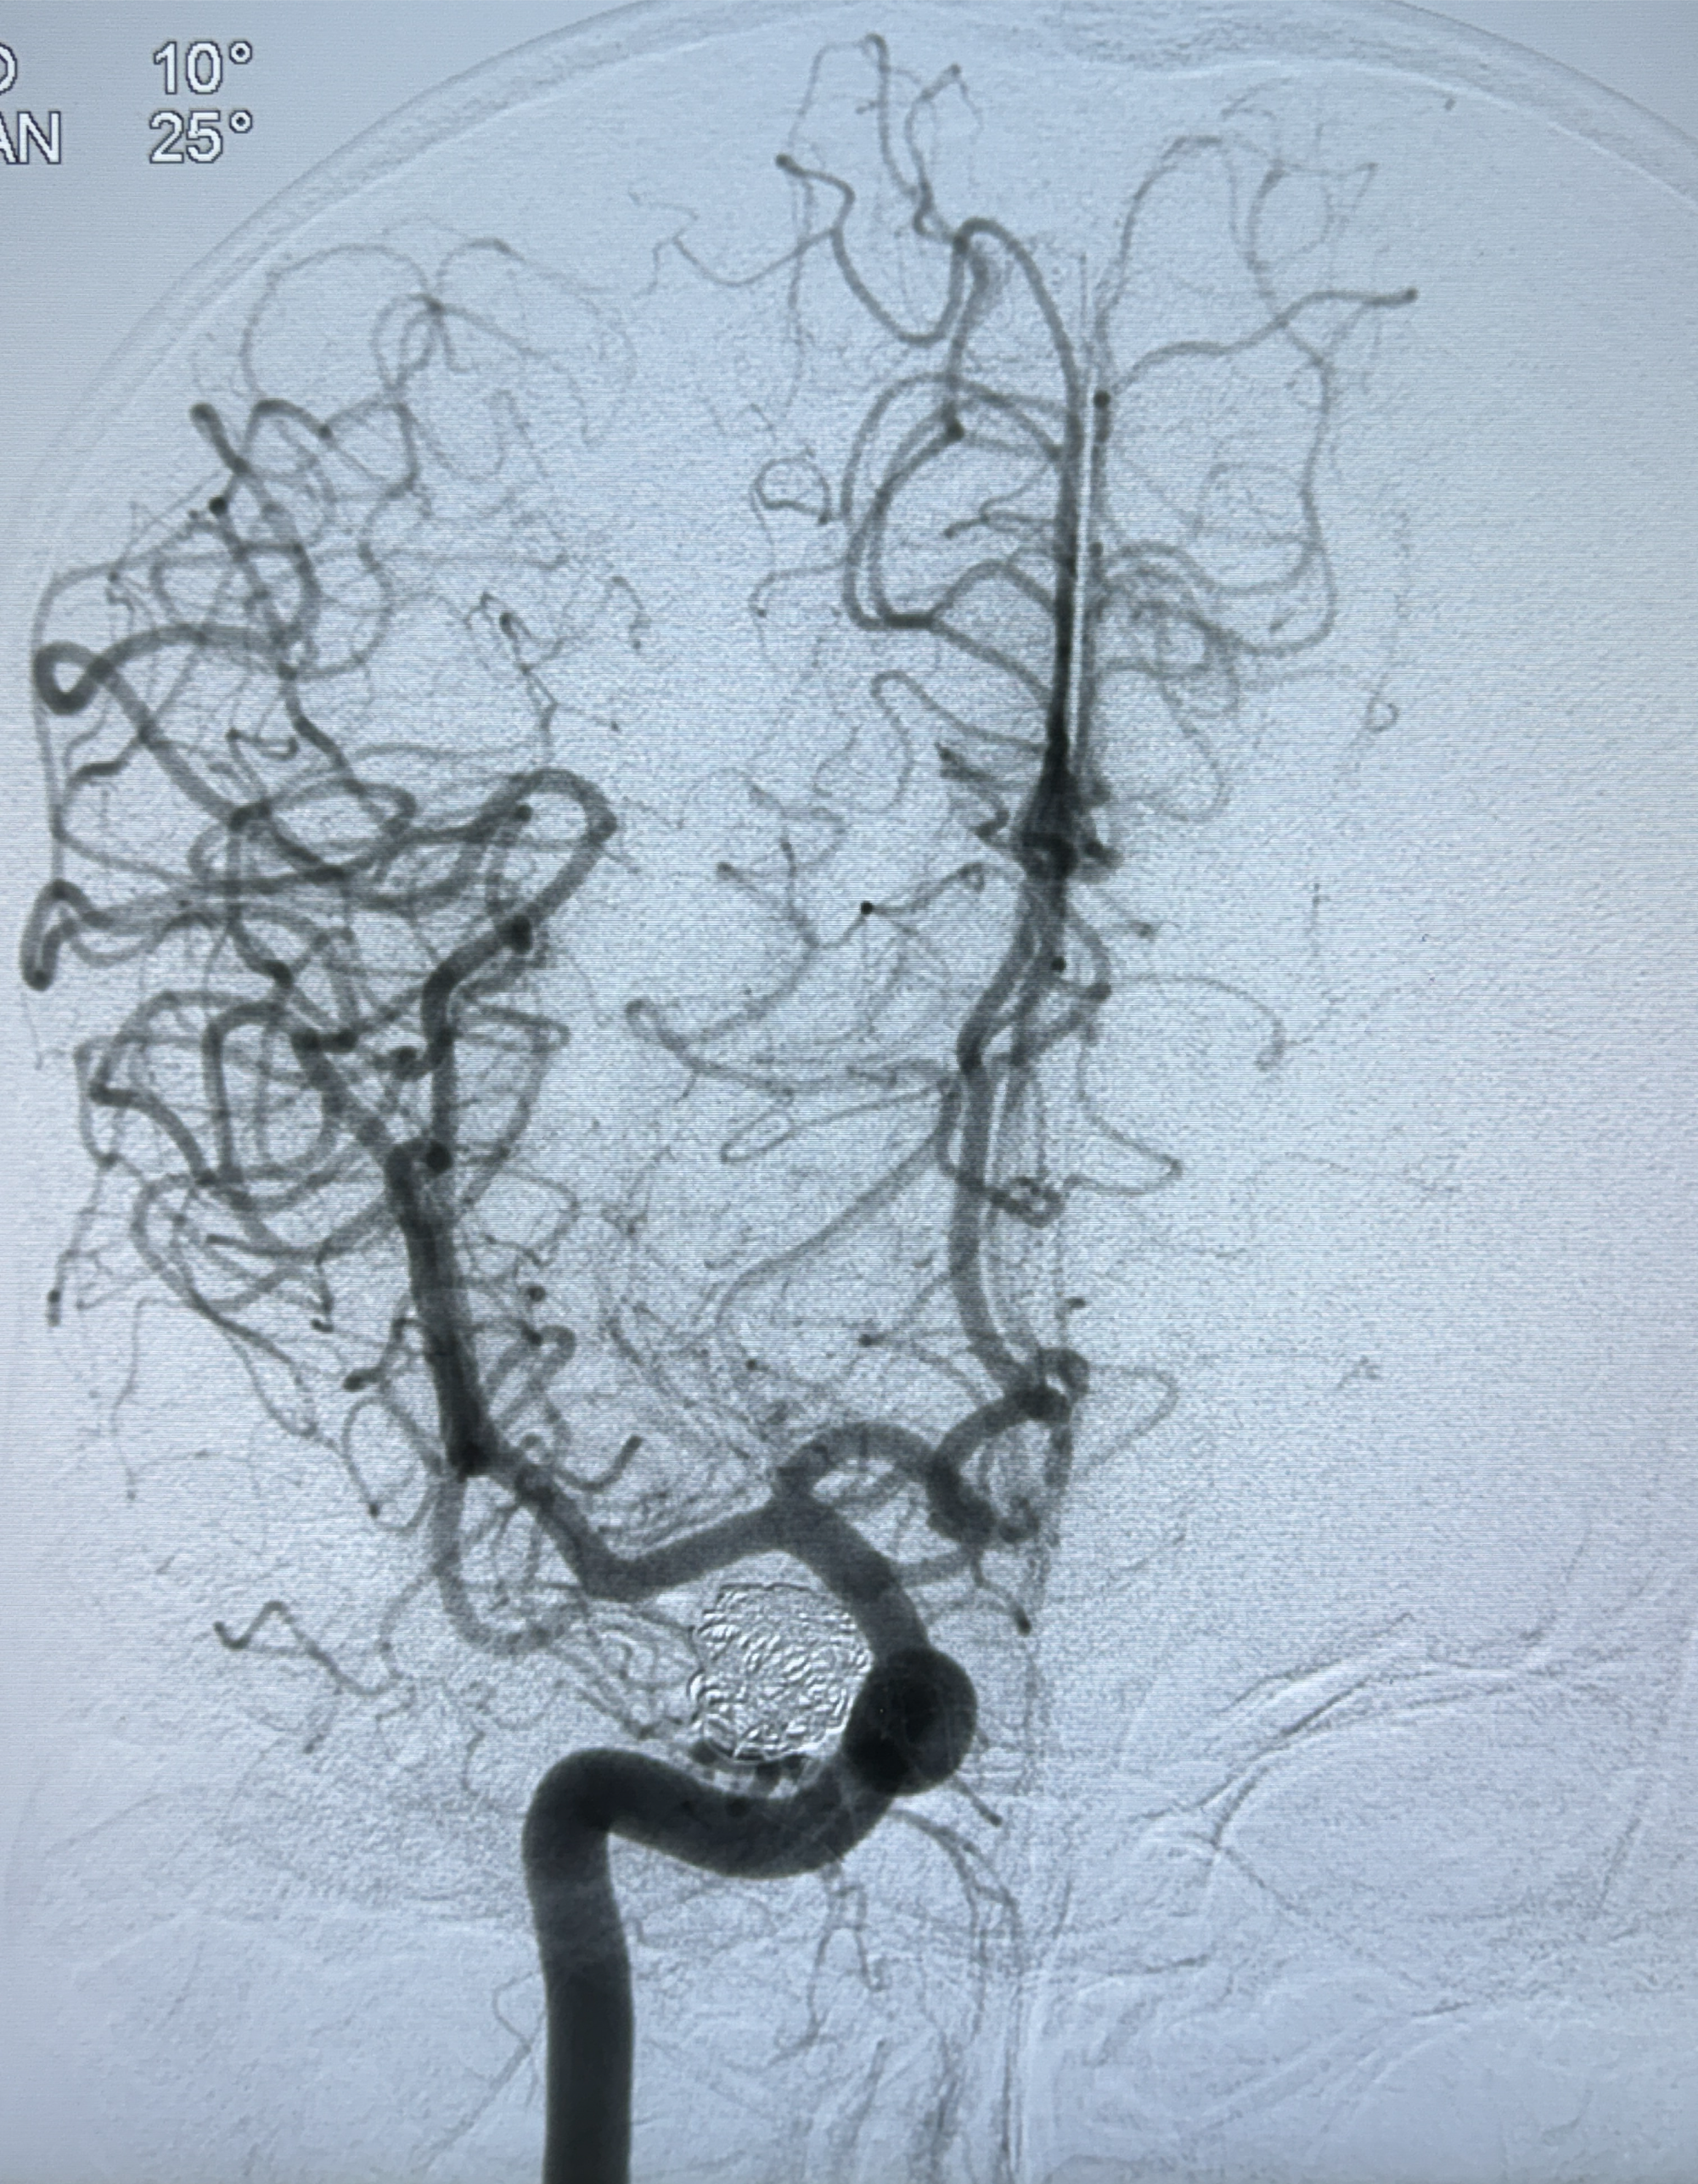

2024-01-08DSA:右侧椎动脉V4段夹层动脉瘤双支架辅助弹簧圈栓塞术后

患者支架辅助治疗后18个月,动脉瘤痊愈